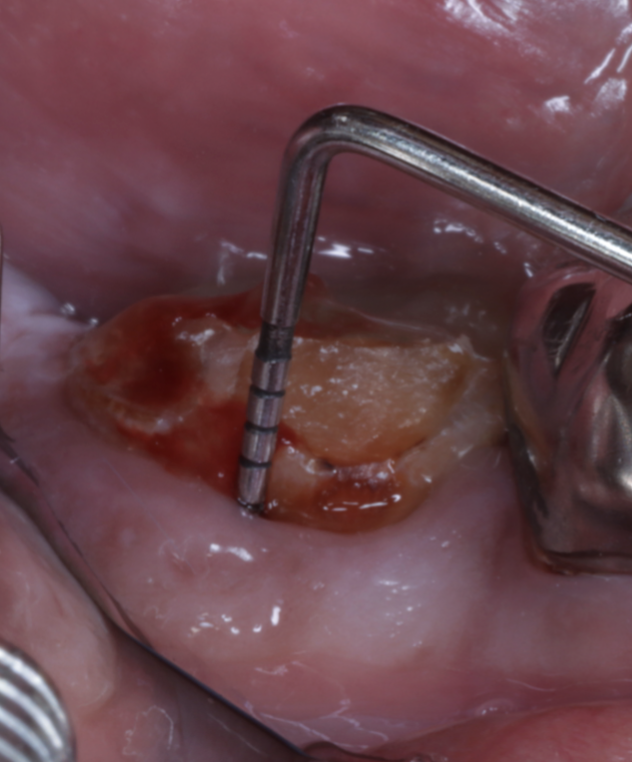

歯周組織再生療法で歯を残した症例

【歯周組織再生療法】

- 担当医

- 生野 誠

- 主訴

- 奥歯の違和感と歯ぐきの腫れを感じて来院。

他院で「抜歯が必要」と診断されましたが、できる限り歯を残したいという希望で当院にご相談いただきました。

- 期間

- 6ヶ月

- 費用

- 40万円

- 治療内容

- 精密根管治療後、以下の流れで再生療法

・感染組織と不良肉芽を除去

・根面滑沢化(バイオフィルム除去)

・エムドゲイン®+骨補填材による再生誘導

・縫合・閉鎖で再生環境を安定化

- 治療に伴うリスク

- 再感染